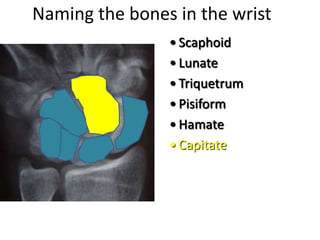

This document provides an overview of hand anatomy including:

- Naming the bones, joints, tendons, nerves and skin landmarks of the hand and wrist.